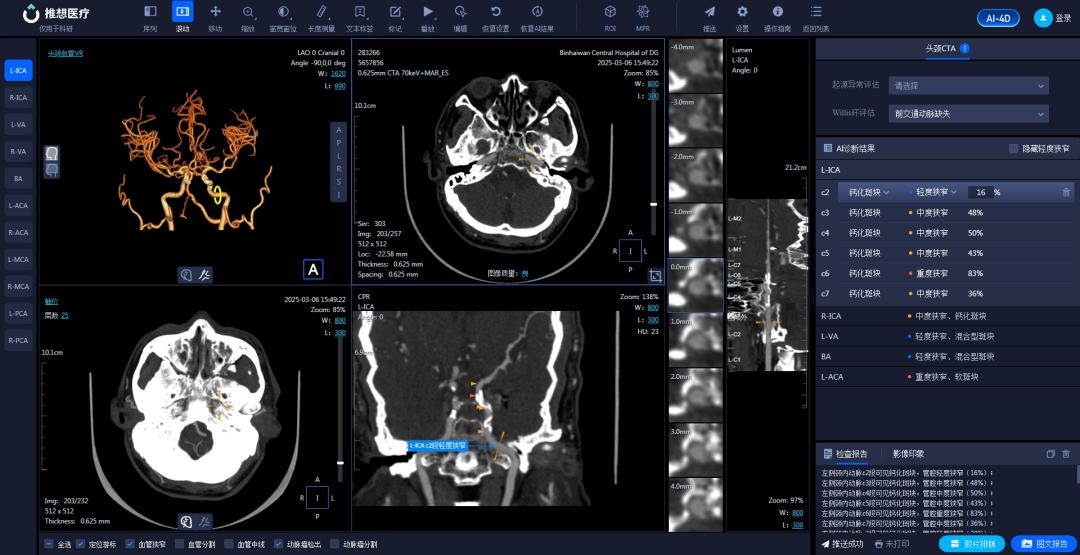

在医学影像科,AI辅助诊断系统宛如一位经验丰富且不知疲倦的医学影像专家,可快速分析肺结节、钼靶检查、骨疾病(骨折)、脑梗塞、脑出血、冠脉CTA(冠状动脉CT血管造影)等影像,提供精准诊断参考,助力医生“一秒读片”。

结合AI技术,256排CT实现去金属伪影、智能心脏重建、一键式卒中流程管理等功能,为心血管疾病和脑卒中患者争取黄金救治时间。